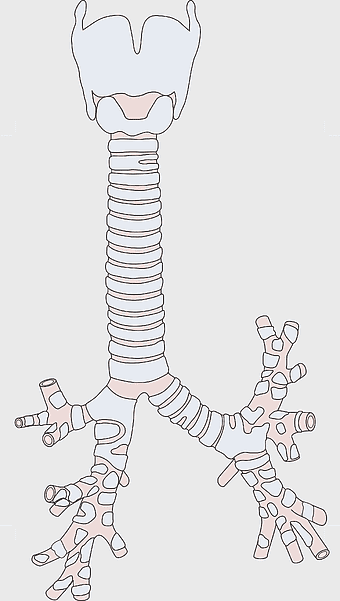

- respiratory system

- lung anatomy

- medical illustration

Bronchus, Trachea, Larynx, respiratory tract anatomy, pulmonary system diagram, medical illustration, airway structure analysis -

Pharynx anatomy, Otorhinolaryngology diagram, Throat larynx illustration, Sinus infection symptoms, Respiratory system, Head and neck medical, Upper airway structure -